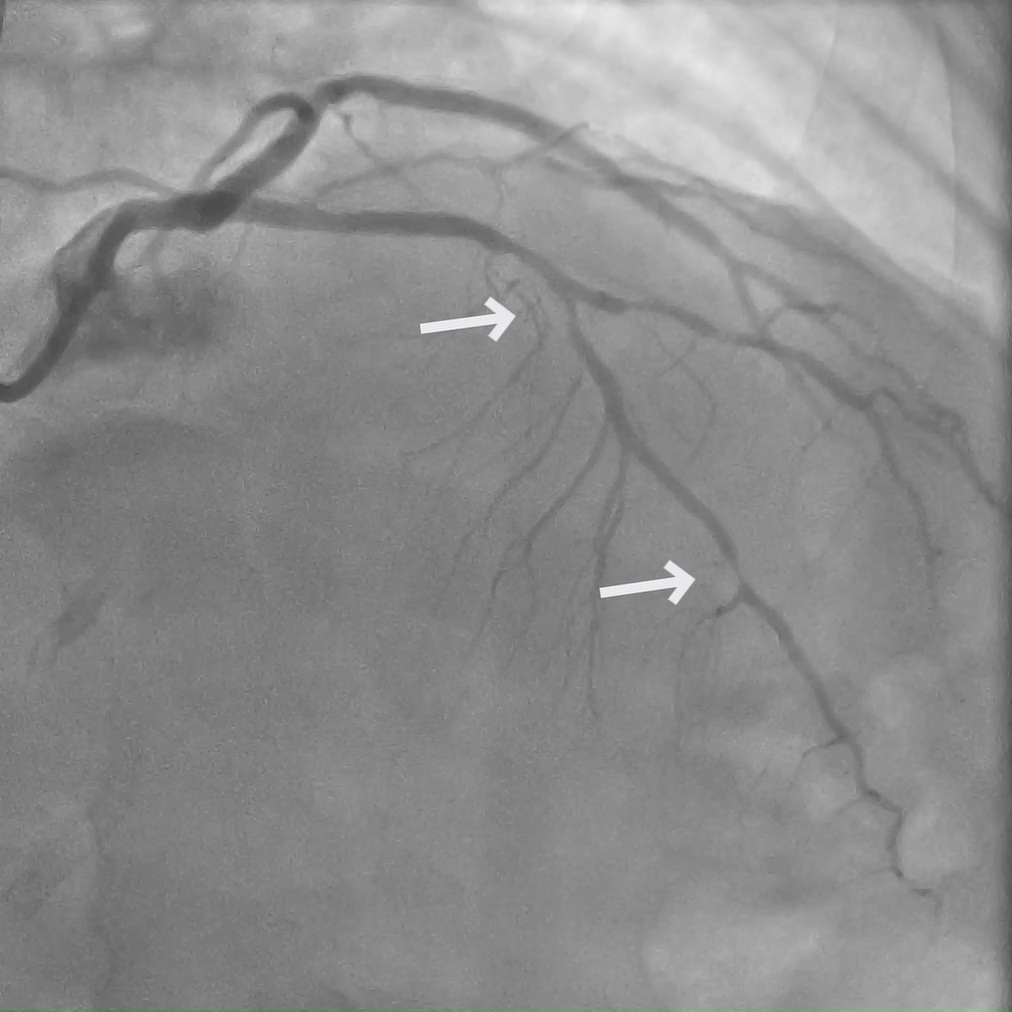

A 55-year-old male with multiple cardiac risk factors presented with worsening chest pain. Myocardial perfusion imaging (MPI) demonstrated ischemia in the left circumflex (LCx) and right coronary artery (RCA) territories.